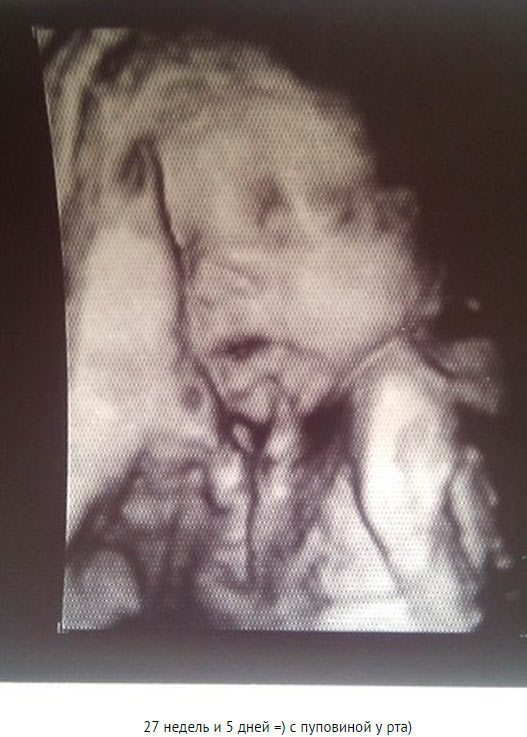

The fetal movements are felt more intensely with each week. Sometimes you may feel like your entire stomach is trembling from the inside. At such moments, it is customary to talk about the hiccups of the fetus. It is believed that children who often suck their fingers often hiccup in the womb.

Ultrasound photo: